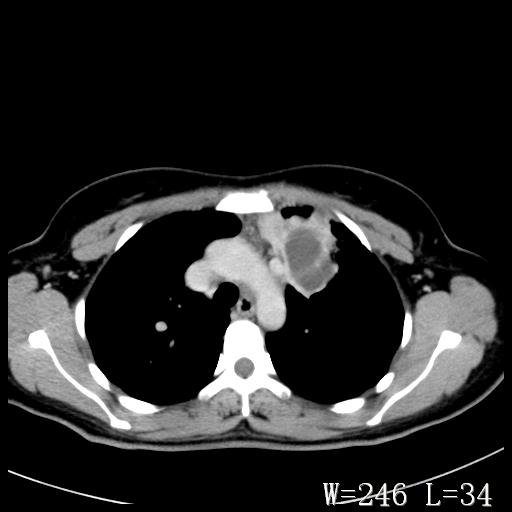

标题: CT27017:1、肺结核?2、永存左上腔静脉。

女,32岁,自述肺结核治疗多年复查。

1)考虑左肺上叶肺脓肿,节段性肺不张。2)永存左上腔静脉。

1)考虑左肺上叶节段性肺不张。原因?2)永存左上腔静脉。

胸骨后偏左侧囊实性病灶,考虑胸腺瘤可能性大.

1、胸骨后偏左侧囊实性病灶,考虑胸腺瘤可能性大。2、永存左上腔静脉。